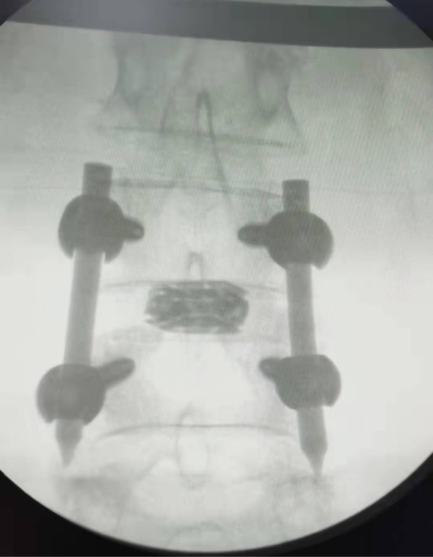

第二天一早,陈建军主任到会泽县中医医院骨伤科进行查房及手术指导。该手术患者为一例长期受腰腿疼痛的老年患者,诊断为“腰椎滑脱(腰4二度)”。陈建军主任为患者行的术式为“全内镜下腰椎微创减压椎间融合技术(PE-TLIF)”,该手术具有创伤小、出血少、费用低、恢复快、并发症少等优势。

手术图示:在腰部做大小如“纽扣”大小的五个小眼,即可完成手术

手术后影像资料